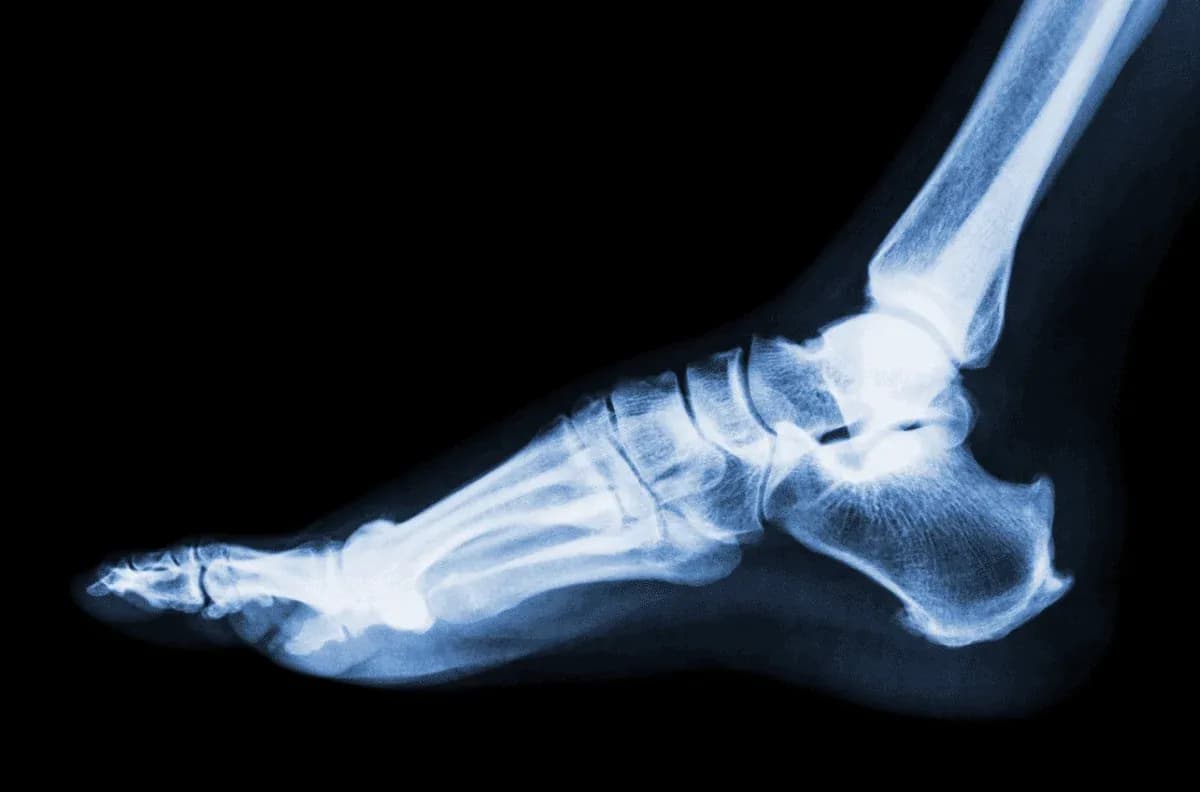

Po skręceniu kostki lekarz może zlecić kilka badań diagnostycznych, aby ocenić stopień uszkodzenia stawu. Najczęściej wykonywanym badaniem jest rentgen, który pozwala na wykluczenie złamań kości. W przypadku podejrzenia poważniejszych uszkodzeń, takich jak naderwanie więzadeł, może być konieczne wykonanie rezonansu magnetycznego (MRI). To badanie dostarcza dokładnych obrazów tkanek miękkich wokół stawu, co pozwala na lepszą ocenę stanu więzadeł i torebki stawowej.